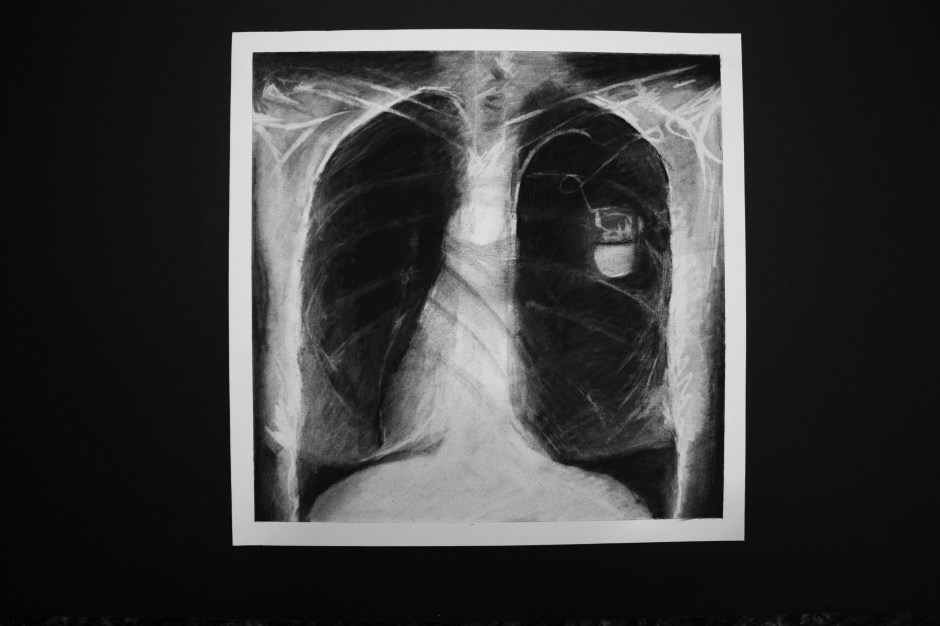

Situs inversus: late diagnosis Date: December 6, 2016Author: saravazquezart Category: Uncategorized Post navigation ← Cemented Pinboard → Situs inversus: late diagnosis Charcoal and pencil on paper 12 x 12in Share this: Share on X (Opens in new window) X Share on Facebook (Opens in new window) Facebook Like Loading... Related